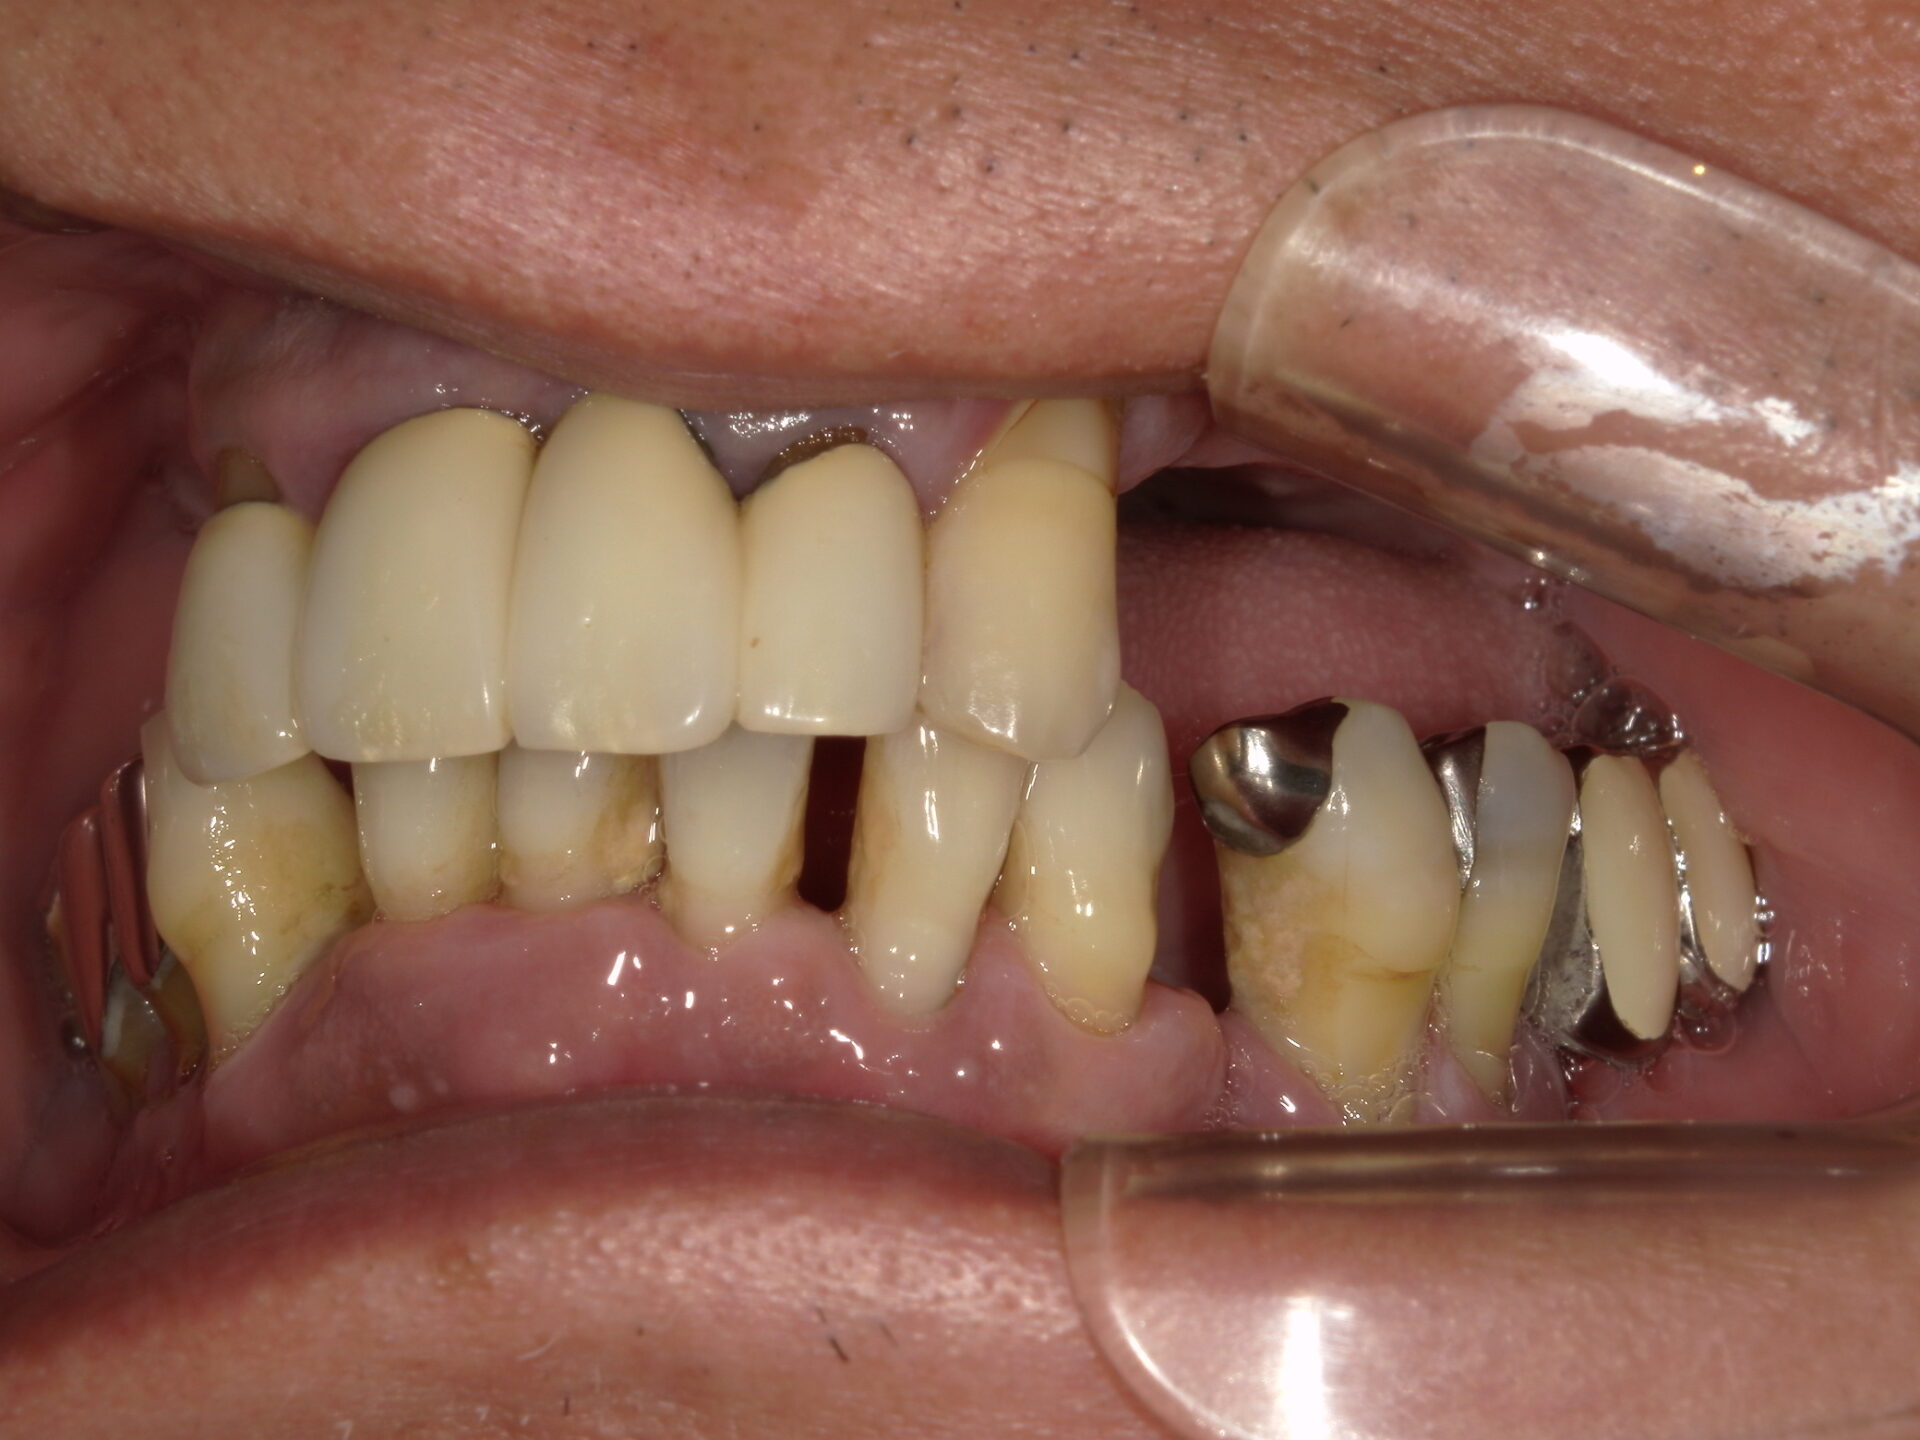

before

after

患者さんの年齢 50代 男性 症状 何も噛めない 治療内容 インプラント治療(オールオン4) 費用 費用900万(税抜) 治療期間・回数 治療期間2年・通院回数12回 メリット なんでも噛めるようになる 見た目が綺麗 デメリット・リスク 骨造成などで費用が増える場合がある - インプラント治療